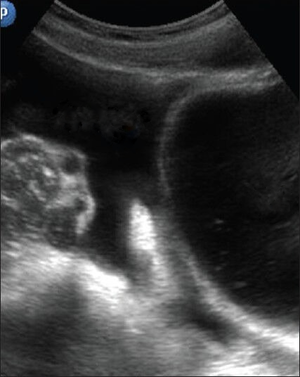

- Identification: anechoic (black) fluid within a structure defined by hyperechoic (white) appearing borders

- Stones

- Twinkle Sign: Rapid alternation of color immediately behind a stationary echogenic object, acquiring a false appearance of movement in color doppler mode

- Can indicate stone in the UVJ

Kidney Stone